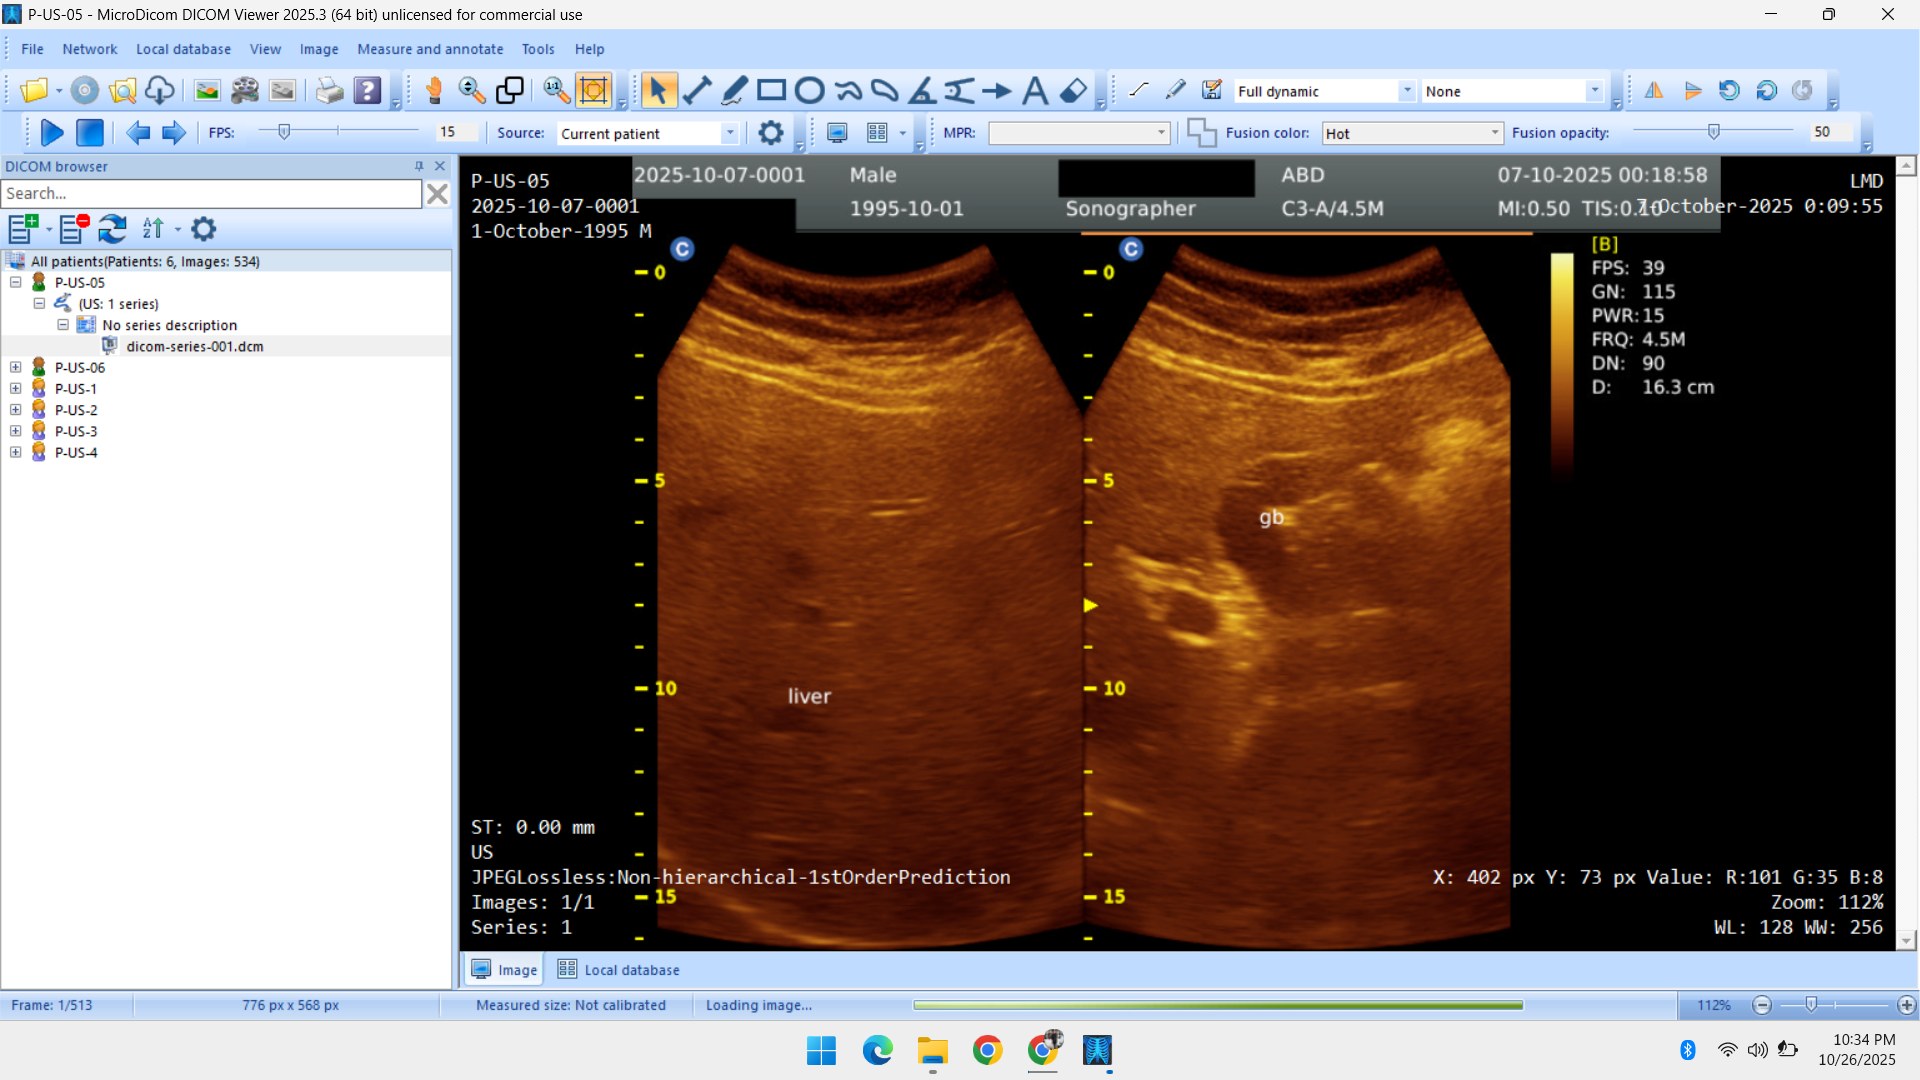

- Radiology Data – CT Scans, X-Rays, MRI, Echocardiography, Ultrasound.

Healthcare & Medical Data Supply

We specialize in healthcare datasets including radiology (CT, X-ray, MRI, Ultrasound, Echocardiography), pathology microscopy, and histopathology images — all ethically sourced and research-ready.

- Ultrasonography